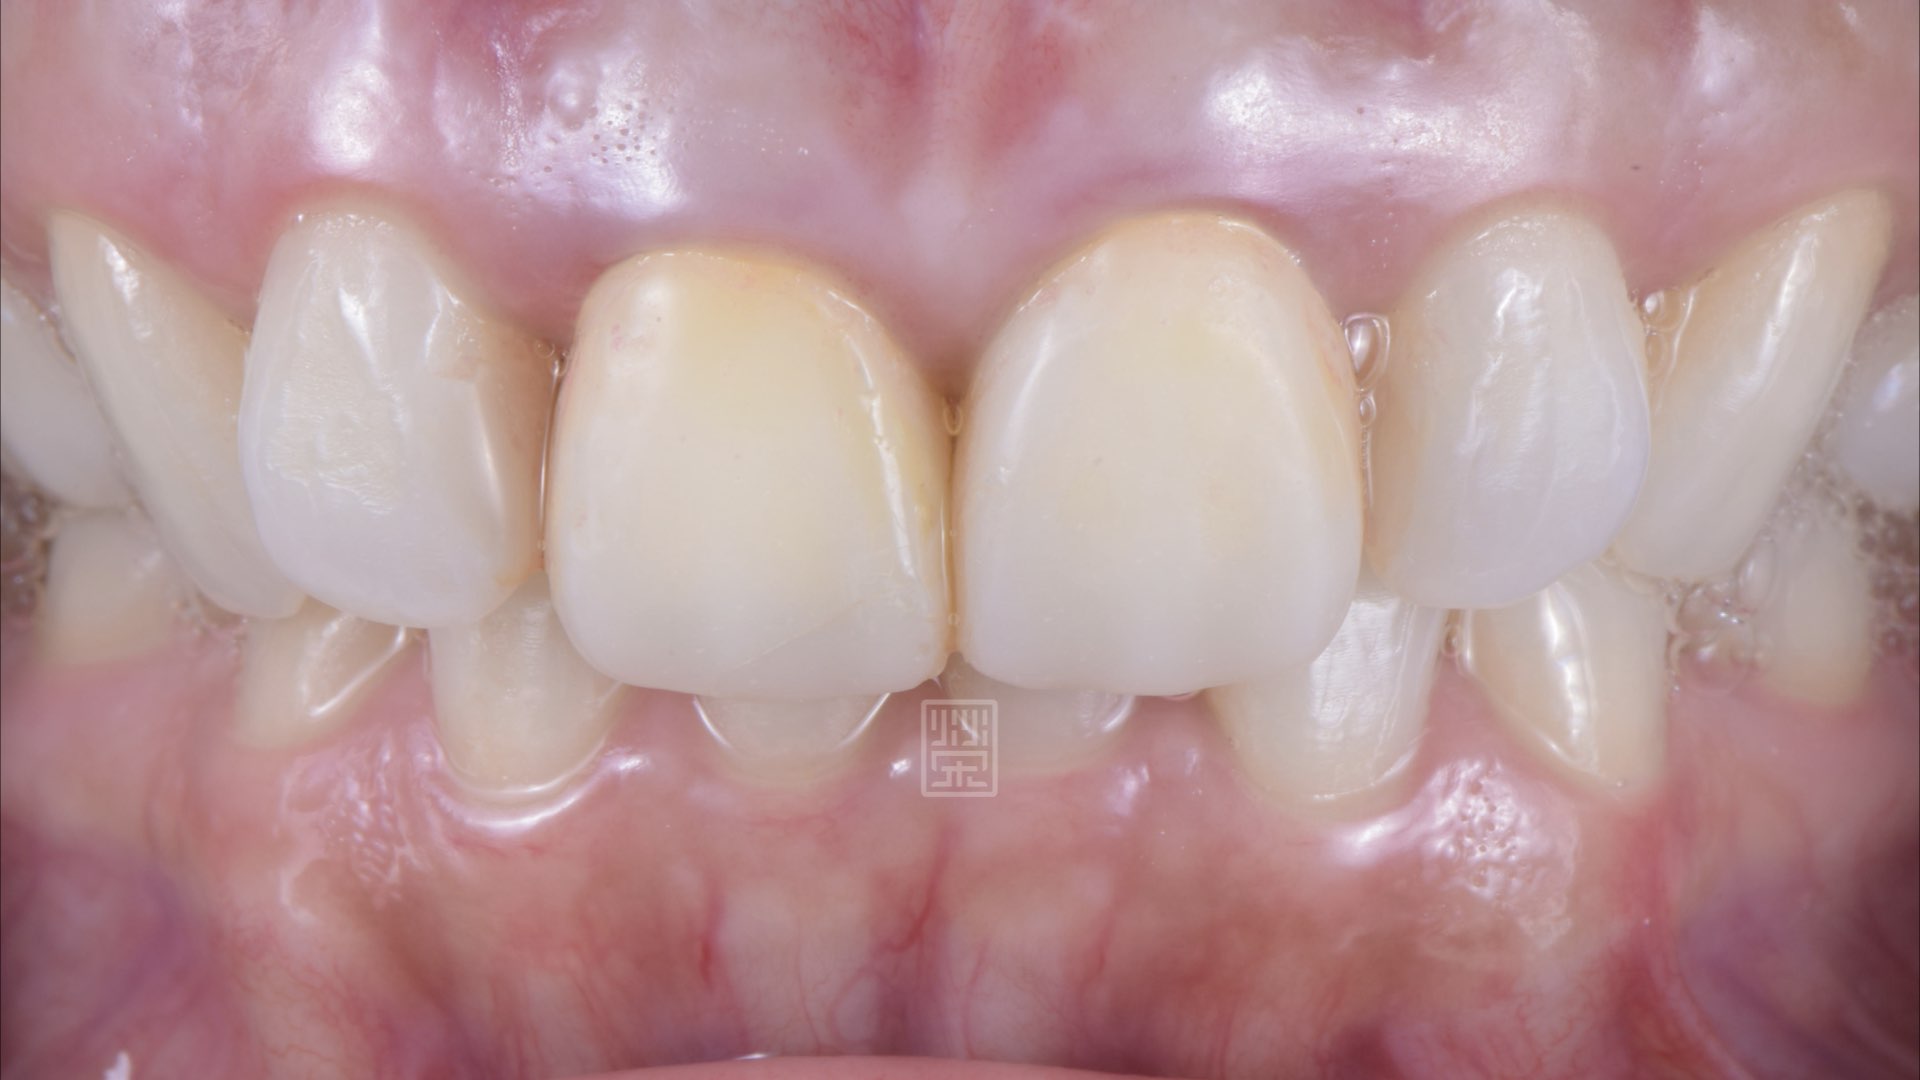

全瓷冠完成